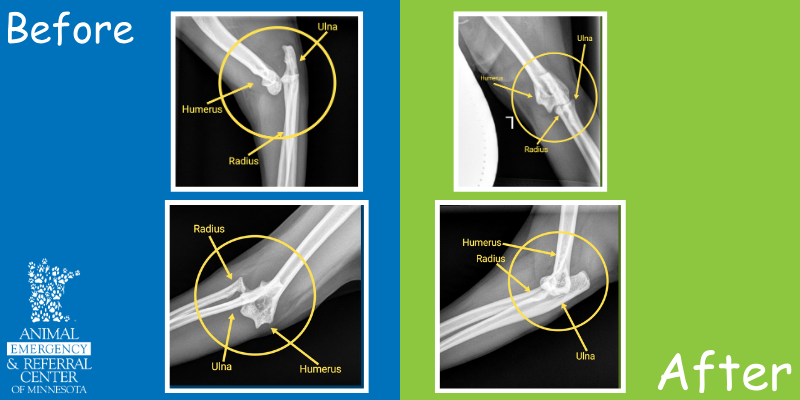

Nova’s x-rays revealed an elbow luxation – which is when the bones that make up the joint of the elbow are not in the right spot anymore.

An elbow consists of three bones – the upper arm bone (humerus) and two lower arm bones (the radius and ulna).

- The ulna sits at the back of the humerus and is responsible for the hinging motion of the elbow.

- The radius sits in front of the ulna at the level of the elbow and allows for the internal and external rotation of the lower arm.

- Think of holding your arm straight out from the elbow and rocking your hand in seesaw motion!

So, in Nova’s situation, her lower arm bones were displaced to the outside edge of the upper arm bone. Fortunately, there were no fractures!

Once Nova was asleep, we gently moved her elbow back into place and took an x-ray to make sure everything looked right. She woke up from anesthesia without any issues and went home a few hours later with pain meds to help with swelling and soreness.